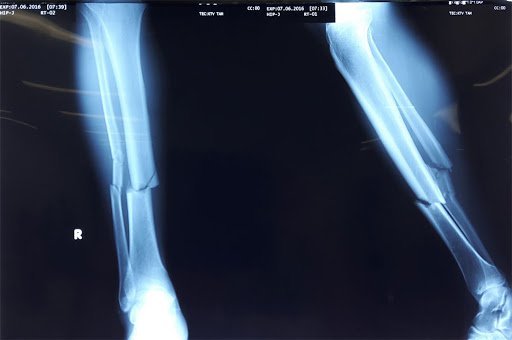

Chụp X-quang là phương pháp xác định rõ nguyên nhân đau cẳng chân

Bên cạnh đó, sẽ có các công nghệ hiện đại hỗ trợ chẩn đoán bằng hình ảnh như X-Quang, cộng hưởng từ MRI…để tìm ra các nguyên nhân gây nên đau cẳng chân như gãy xương, viêm gân…